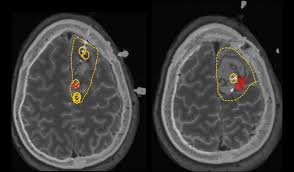

Le traitement chirurgical

En cas d’épilepsie pharmacorésistante, c’est-à-dire lorsque des crises d’épilepsie persistent malgré un traitement médicamenteux bien pris, une intervention neurochirurgicale peut être envisagée, en fonction de :

la fréquence et l’ancienneté des crises épileptiques ;

leur retentissement sur la vie du patient ;

l’existence d’un foyer épileptogène précis (zone cérébrale où se déclarent des crises récurrentes, liées par exemple à une tumeur ou une malformation engendrant des lésions).

Avant toute intervention, on réalise un bilan approfondi pour mieux localiser le foyer épileptogène et vérifier s’il peut être enlevé, sans risque de handicap lié à l’ablation d’une zone du cerveau.

Pour réaliser ce bilan, on utilise l’imagerie cérébrale fonctionnelle (ensemble de techniques d’imagerie médicale permettant d’analyser le fonctionnement du cerveau). Une fois le bilan de l’épilepsie terminé, la décision thérapeutique est prise par une équipe pluridisciplinaire (chirurgien, neurologue, neuropédiatre, radiologue).